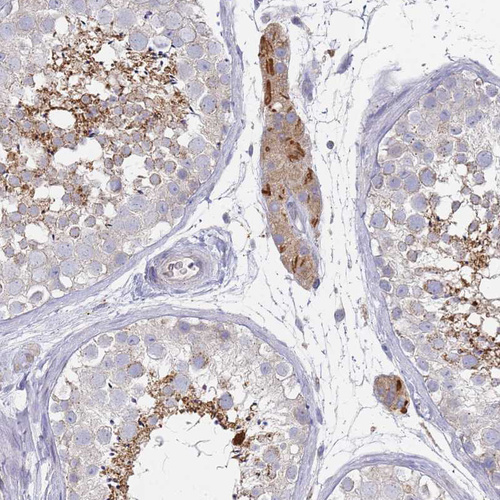

Immunohistochemical staining of human duodenum shows moderate cytoplasmic positivity in glandular cells.